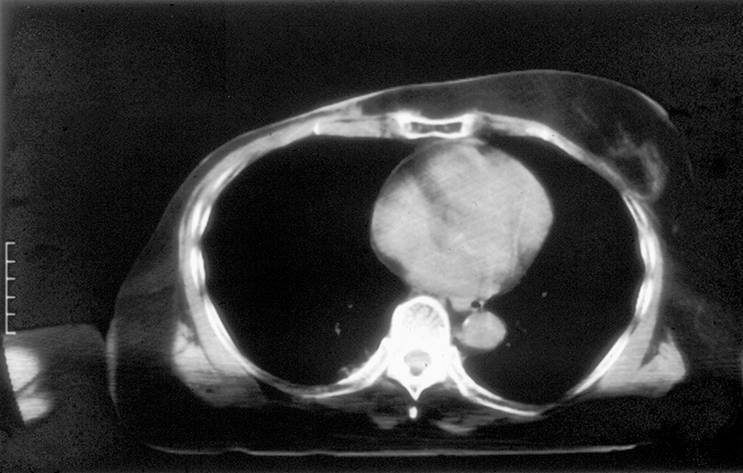

Accomplishments that I'm proud of The concept of a wearable multi-antenna array that includes non-invasive thermometry with a thin and flexible fiberoptic sensor array fitting the inner surface of the vest, and subsurface monitoring of tumor temperature with microwave radiometry. These concepts have attracted previous NIH funding sufficient to complete theoretical optimization of the applicators and integrate the heating array with a comfortable elastic fabric covered waterbolus compartment that effectively cools the skin and avoids potentially painful hot spots. Several different size prototype microwave vest applicators have been assembled and tested in a 14 patient clinical trial. The published results demonstrate significantly improved extent of heating over the best alternative heat applicator, along with improved comfort for the patient.

What I learned The microwave vest effectively heats large areas of chest wall, while being more comfortable for the patient than alternative box shaped applicators that do not conform well to the tissue surface. All aspects of the required heating system are technically feasible and just need a commercial enterprise to build and obtain regulatory approval to use the new device. The device will be particularly suitable for drug companies with temperature sensitive drug carriers and for thermal oncology treatment centers that need uniform heat application to sensitize recurrent tumor treatments to radiation and/or chemotherapy.